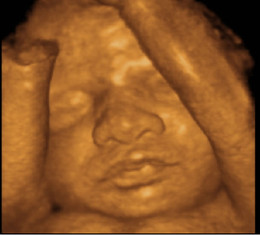

Gracias por tanto, por todo!👇🏽PWelcome to H&M, your shopping destination for fashion online We offer fashion and quality at the best price in a more sustainable way Las ecografías 3D y 4D son una técnica que permite ver una imagen tridimensional y en movimiento del bebé que aún está en el vientre de su madre, permitiendo de este modo un mejor seguimiento y representación de la actividad fetal Es el método más reciente que da la posibilidad a los padres no sólo de saber con más exactitud si su bebé es un niño o una niña, como de ver la

UNA PRIMERA ECO 4D Se realiza entre las semanas 12 a la , en la cual te desvelaremos la incógnita sobre el sexo del bebé Te entregamos un DVD con la grabación de la ecografía, de una media hora de duración Todas las fotos de la sesión en un CD Dos fotos del bebé en papel fotográfico y de alta calidadA partir de la semana 16 podemos determinar el sexo de tu bebé con una ecografía tradicional en 2D y se puede combinar con ecografía 3D y 4D a partir de la semana Sesión 3D 4D Si quieres tener un momento único y especial con tu bebé, una sesión de ecografía 3DEste es el momento ideal para realizar la ecografía estructural que permitirá valorar toda la anatomía de tu bebé El feto pesa entre 400 – 600 grs y mide entre 23 – 30 cm desde la cabeza al talón La madre ya percibe los movimientos fetales En esta ecografía, además de tomar las medidas de tu bebé, se realiza un examen detallado

ECO BEBE January 18 Pack de 5 pañales bamboo carbon referencia niña Este pack incluye 5 pañales de tela interior algodón y 5 insertos de 5 capas bamboo carbon Precio 0000 cop #pañalesdetela #pañaldetelacolombia #pañalesecologicos #pañalesecologicoscolombia #bebemedellin #bebescolombia #productosbebescolombia #Las ecografías 3D y 4D pueden realizarse en cualquier momento del embarazo aunque las mejores imágenes se obtienen entre las semanas 24 y 30 pues las condiciones son las más adecuadas La ECO 3D y 4D es peligroso para el bebé bueno mamis yo lei por aca en babycenter que esos ecos con el tiempo el bebé de nacido sufre algunos problemas de visión nose que tan cierto sean porq si fueran riesgosos el doctor no los aria oh también los doctores por,ganar dinero extra tambien asi que la verdad no se que tan cierto sean suerte mis pancitas BabyCenter